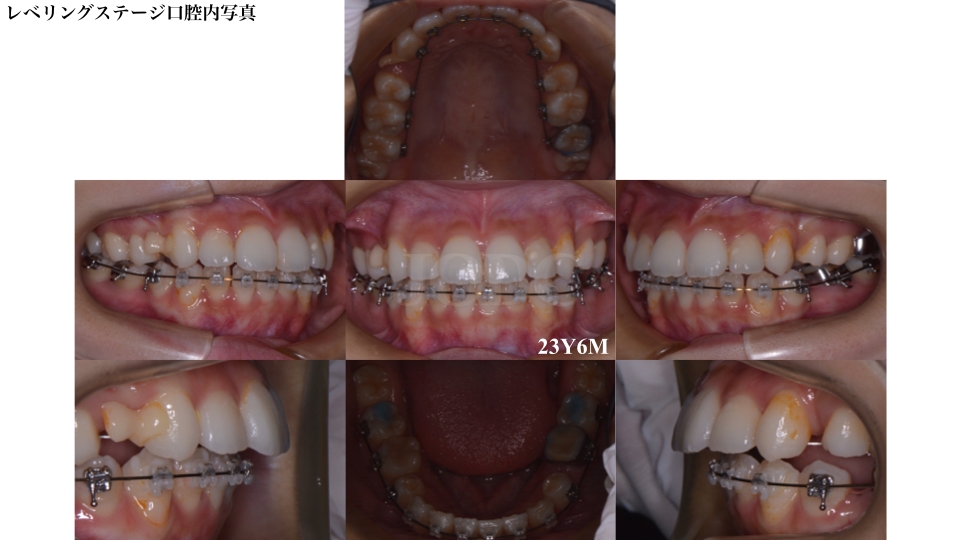

レベリング(デコボコの改善)ステージです。